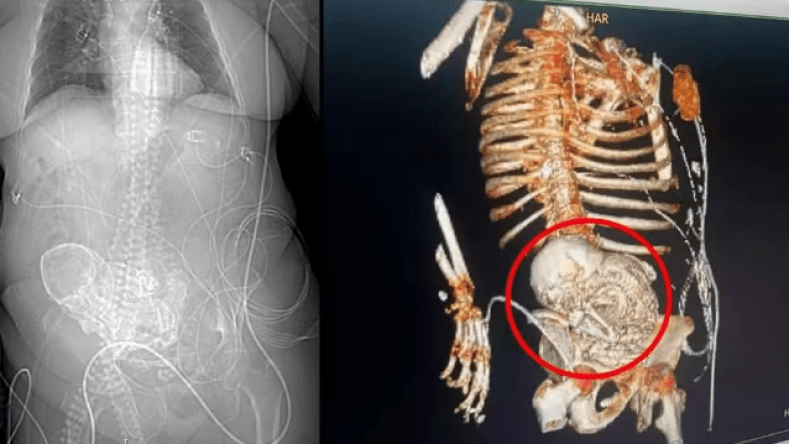

ووجد الأطباء، بواسطة عمليات المسح بالأشعة المقطعية، “الجنين المتحجر”، أو كما يعرف أيضا باسم “الجنين المتكلس” (lithopedion)، والذي كان موجودا في جسد والدته لمدة 56 عاما.

ويعرف “الطفل المتحجر” بأنه ظاهرة نادرة تحدث بداية من 14 أسبوعا من الحمل، عندما يموت الجنين أثناء الحمل البطني، ويكون أكبر من أن يعاد استيعابه من قبل الجسم، وبالتالي يتكلس من الخارج كجزء من تفاعل غريب يحمي جسم الأم من النسيج الميت من الجنين ويمنع العدوى.